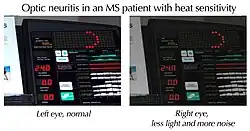

Patients with optic neuritis may experience dyschromatopsia which describes a range of color vision in the affected eye (especially red), with colors appearing subtly washed out compared to the other eye. Patients may also experience difficulties judging movement in depth, which can be particular troublesome during driving or sport (Pulfrich effect). Likewise, transient worsening of vision with increase of body temperature (Uhthoff's phenomenon) and glare disability are a frequent complaint.